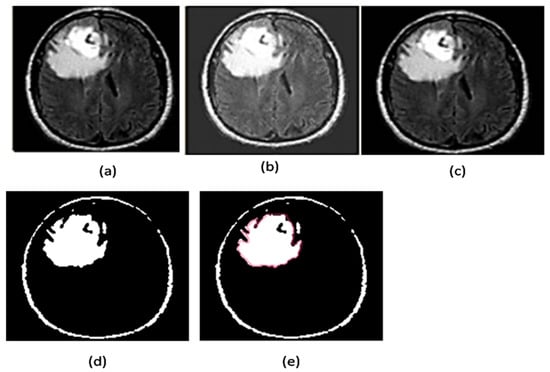

2.2.7. Area Segmentation using Watershed Algorithm

2.2.8. Region Masking and the Separation

2.3. Proposed a Colorized Method for Masked Area Colorization